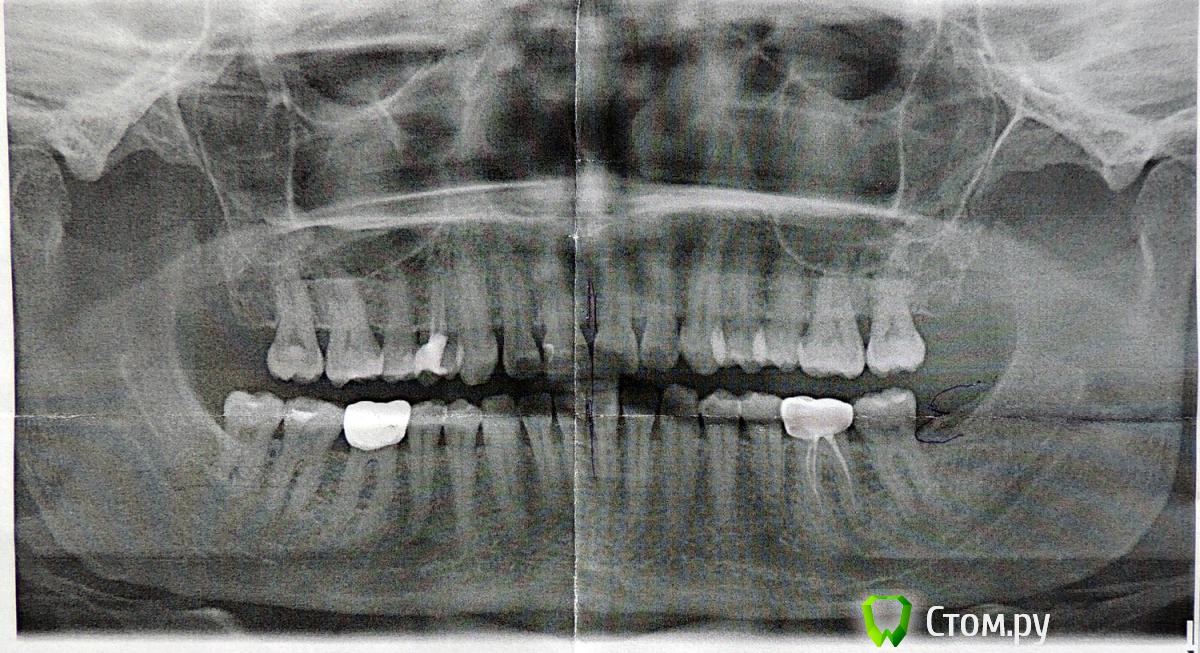

umishka Опубликовано 30 декабря, 2013 Поделиться Опубликовано 30 декабря, 2013 Добрый день. Ситуация такая. Заболел зуб под коронкой, решила пойти снять коронку, чтобы обследовать зуб, подлечить его и снова закрыть коронкой. Перед этим сходила на гигиеническую чистку зубов - сняли камни. Гигиенист о состоянии дёсен ничего плохого не сказала. Затем я пошла в терапевту, который сделал панорамный снимок (во вложении), снял коронку. Сказал, что дёсны в плохом состоянии, глубокие десневые карманы - на последних верхних зубах слева до 9 мм. И посоветовал обратиться к пародонтологу. Пародонтолог сказал, что нужна операция справа и слева - вскрыть дёсны, прочистить карманы, зашить. Про наращивание кости ничего не говорил, только про чистку. Подскажите, нужна ли на самом деле операция? Меня удивило, что не назначили никакого иного лечения - ни мази, ни полоскания. Ссылка на комментарий

IvanK Опубликовано 30 декабря, 2013 Поделиться Опубликовано 30 декабря, 2013 Здравствуйте,я бы не спешил с операциями. Проф.гигиена + обучение гигиенеПовторное лечение, с последующим протезированием 14,36,46 1 Ссылка на комментарий